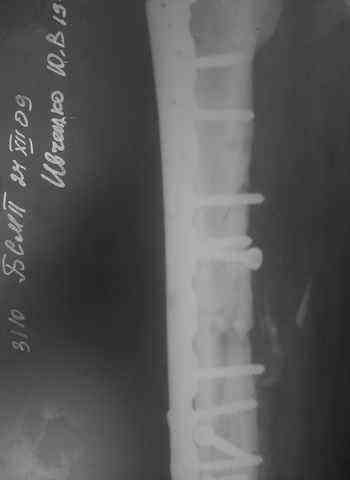

Несрошийся открытый фрагментарный,оскольчатый,перелом в/с/3 правого бедра

Несрошийся открытый фрагментарный, оскольчатый, перелом в/с/3 правого бедра с размозжением мягких тканей.

Состояние после ПХО,МОС,ВО ЧКФ стержневым АВФ.

10.10.09.Заживление раны per prima.

Операция:16.12.09,открытый накостный МОС,аутокостная пластика(из крыла подвздошной кости)правого бедра. После п/о периоде заживление раны вторичным натяжением (на 5-е сутки распущены швы, после очищения раны наложины вторичные швы) На этапных RO-гр:остеолизис костного трансплантата и дистального фрагмента перелома бедра.

Вопрос:дальнейшая тактика лечения-БИОС аутокостная пластика (трансплантат на сосудистой ножке М/Б кости). Билокальный остеосинтез по Илизарову с остеотомией подвертельной и надмыщелковой области бедра.

Мозможен ли аутотрансплантат без сосудистой ножки? Чем улучшить васкуляризацию? Декортикация? Тактика выжидания остеолизиса, а затем оперативное лечение.